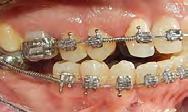

14 para la caracterización del canino 13, (Figura 6) IPR y elásticos clase III para corrección de overjet, elásticos asimétricos y uso de microtornillos de 2 × 14 mm en cresta infracigomática izquierda para corrección de línea media, arcos de acero 0.017 × 0.025 y 0.019 × 0.025 con dobleces de primer, segundo y tercer orden para detallado, retención a cargo de retenedor fijo inferior de 3 a 3, retenedor circunferencial superior y termoformado inferior.

El tiempo del tratamiento fue de 2 años 11 meses, en la Figura 7 en los

estudios extraorales finales se ve la mejoría en la sonrisa y de los tejidos blandos en cuanto al perfil facial.

Estudios intraorales finales: se observa en la Figura 8 y 9 la mordida del paciente en oclusión las lineas medias coincidentes, formas de las arcadas oval, la obturacion del molar 26, la clase I canina y molar izquierda, clase I canina derecha, caracterización de premolar 14 por canino 13, clase I molar derecha y espacio en el cuandrante 4 el cual se utilizará para rehabilitación protésica.

Estudios radiográficos finales: se observa en la Figura 10 en la

radiografía lateral de cráneo la mejoría en la inclinación del incisivo inferior.

En las radiografías panorámicas (Figura 11), en la comparación inicio el botón de Nance, en la final se ve sin el canino retenido, el paralelismo radicular, con la ligera perdida ósea con la que llegó la paciente en la zona antero inferior y cuadrante 4, al final continúa sin cambios.